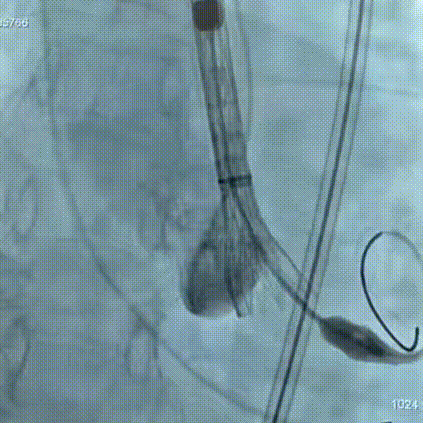

手术过程:在右股动脉穿刺建立通路后,顺利送入大鞘,经食道超声及血管造影确认路径稳定。18mm球囊预扩后评估冠脉灌注良好,后将Prostyle A® AV26瓣膜精准释放于目标位置,超声显示无瓣周漏,术后即刻造影显示无明显反流,术前PGmean40mmHg,术后导管测平均跨瓣压差8mmHg,心功能明显改善,患者生命体征平稳。

主动脉根部造影

定位

迅速锚定

最终造影形态位置良好,无瓣周漏